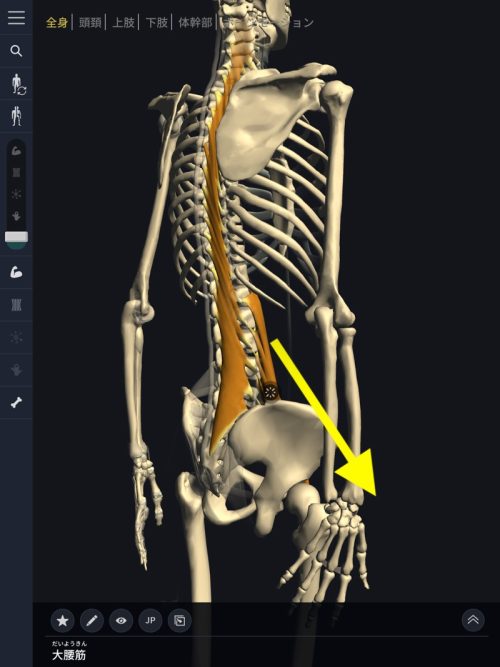

多裂筋に硬直により上と下に引っ張り合う

硬直した筋肉は固くなり縮む習性がありますので、多裂筋の硬直により背中が凝る(固まる)または上方向に腰椎を引っ張る状態が発生します。

この状態で大腰筋が硬直すると大腰筋が腰椎の付着部分を下方向へ引っ張るので多裂筋と上と引っ張りっこになり間の椎間板が耐えられず飛び出してヘルニアになるのです。

拡大してみてみるとこのようになっています。

この状態なら骨と骨の間に圧力が加わって軟骨が飛び出すのも納得ですし、他のどのヘルニアの原因解説よりも整合性があると思います。

下の図のように腰の筋肉は骨盤だけでなく足や背中、腕にも繋がっています。その為、腰だけを診る治療法や骨盤の歪みだけを診る治療法や筋膜、骨格などを主に診る治療法では見落としてしまう部分があり、それがヘルニアの腰痛がなかなか治らない原因の1つにもなっています。

毎日のお仕事や家事などで披露が蓄積すると筋肉は硬直し縮んで黄色い矢印の方へ引っ張る力が生まれます。腰を中心に上にも下にも引っ張られることで、骨盤に歪みが生まれたり腰椎を圧迫してヘルニアになったりします。

この図のように腰に連携している筋肉は多数あり、それらの筋肉が硬直して縮むことにより筋肉の末端が付着している骨盤などの位置にズレが生じ痛みを生み出しているのです。

例えばこの図のように背中や肩が張っていて動きが悪い状態の時に太ももが硬直して縮んだ場合には下方に引きずり込まれる形になり筋肉のズレが生じて骨盤までが歪んで腰に痛みがでます。

例えば肩こりや首コリが酷い場合に、長時間座っていたり、中腰や屈伸などの脚への負担が大きい場合には、この図のように上下に縮んだ筋肉が引っ張り合うので中間部分の腰に痛みが生じます。